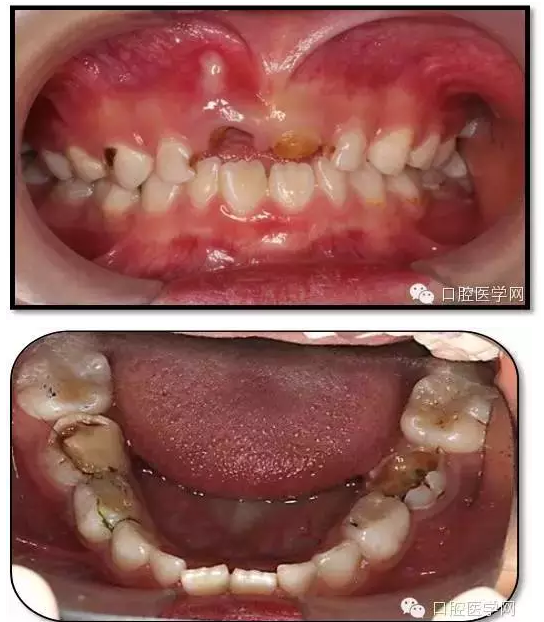

患兒,女,6歲1個月

主訴:坐下后牙頰側(cè)牙床鼓膿包2周

現(xiàn)病史:左下后牙頰側(cè)牙床鼓膿包2周,左側(cè)進(jìn)食疼痛,來診求治?;純簭?歲開始刷牙,父母幾乎不幫助刷牙。從沒用過牙線,愛吃甜食,偶爾睡前吃甜食。雙側(cè)下后牙1年前在我院兒科行根管治療。

既往史:84、85、75在1年前我院兒童口腔科行根管治療史。

查體、輔查

臨床檢查: 75OL齲洞, 舌側(cè)牙體完全劈裂斷端齊齦,探及大量軟化腐質(zhì)。頰側(cè)牙齦紅腫見瘺管,擠壓大量溢膿。叩(±),不松動。X線:75根管空虛,牙根吸收約1/2,根尖周及根分歧大面積透射影,35發(fā)育4期,骨硬板尚連續(xù);51殘根,唇側(cè)牙齦瘺管,叩(±),不松動。X線:51牙根吸收約1/2,根尖周低密度影。

85O、84DO充填體邊緣不密合,叩(±),不松動。84頰側(cè)牙齦略紅腫。X線:84遠(yuǎn)中根及髓室底完全吸收,根分歧透射影,近中根內(nèi)側(cè)見外吸收,44上方骨硬板連續(xù)。85近中根完全吸收,髓室底吸收,根分岐透射影,遠(yuǎn)中根管內(nèi)見根充影像。45發(fā)育4期,骨硬板連續(xù)。

55OL、65OL、74O、53DL齲洞,叩(-),不松動,齦無異常。

16OL、46OB、26O、36OB窩溝探及淺齲壞,叩(-),不松動,齦無異常。